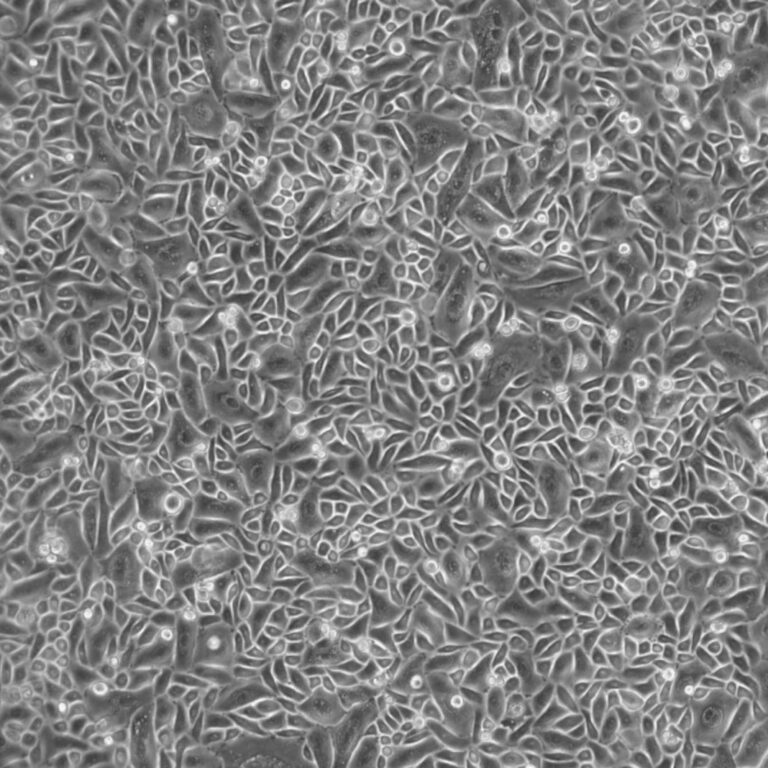

From www.lifelinecelltech.com

Primary Small Airway Epithelial Cells Diseased Why Is My Airway Small smaller airways are supported by the lung tissue that surrounds and is attached to them. These tests measure how well your lungs are working. small airways disease is associated with poor spirometry results, increased lung hyperinflation, and poor health status,. What should i do if i am wheezing? One common test is spirometry,. an abnormal growth in. Why Is My Airway Small.